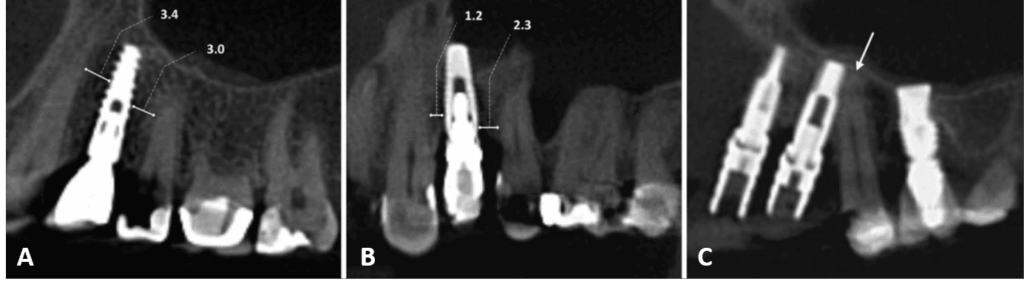

Errores de posicionamiento de implantes dentales en relación con estructuras anatómicas en el maxilar superior

Los implantes dentales constituyen una alternativa eficaz para la rehabilitación bucodental y contribuyen a la calidad de vida de los pacientes. No obstante, el procedimiento de colocación de implantes no está exento de errores técnicos, que pueden producirse como consecuencia de fallos en la planificación quirúrgica o en la identificación precisa de las estructuras anatómicas....